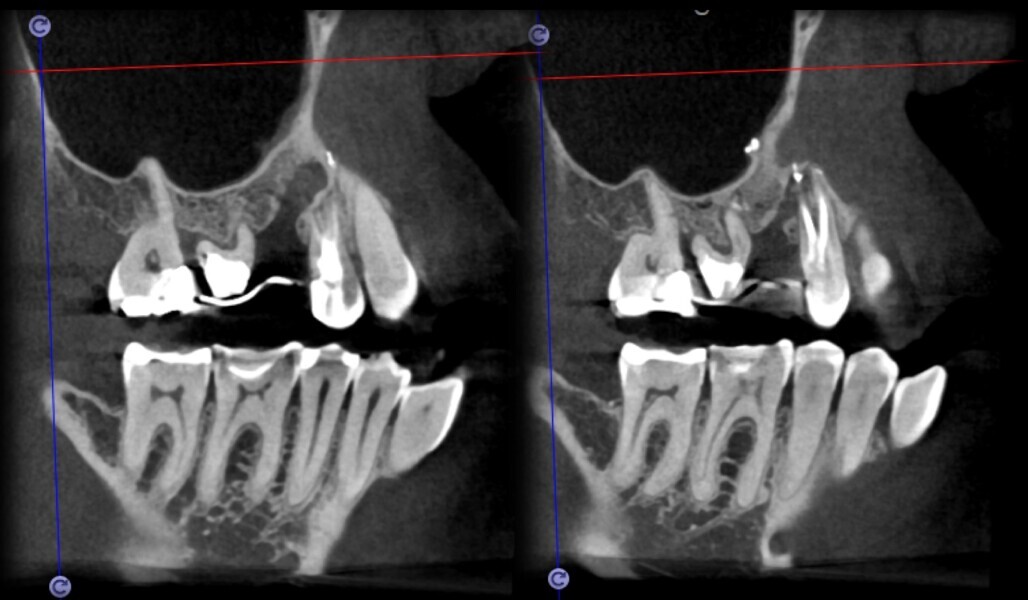

Use of 3D technology in the diagnosis and treatment of endodontic disease